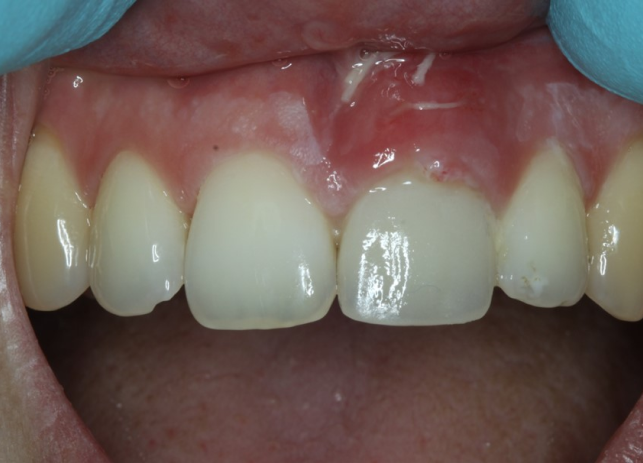

Рис. 9 и 10 после начального заживления временная коронка была адаптирована с помощью композита для тренировки и формирования мягких тканей, аналогично прилегающему правому центральному резцу. Нашей целью также было добиться одинаковой длины 11 и 21 зубов или выровнять высоту десны